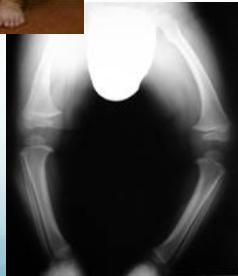

Blount’s Disease

Rickets

Rickets - Improves with time